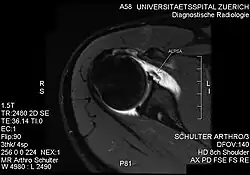

| PD-weighted MRI with fat saturation of the shoulder showing an ALPSA lesion |

An ALPSA (anterior labral periosteal sleeve avulsion) lesion is an injury at the front of the shoulder associated with shoulder dislocation.[1]